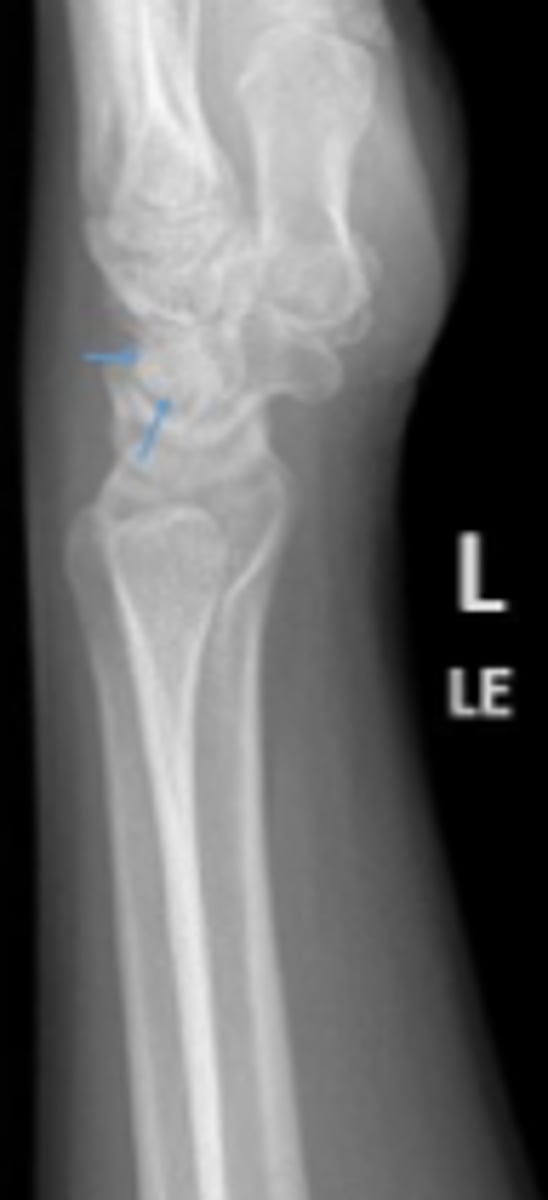

Medial oblique of the left wrist

What is the name of the radiographic view?